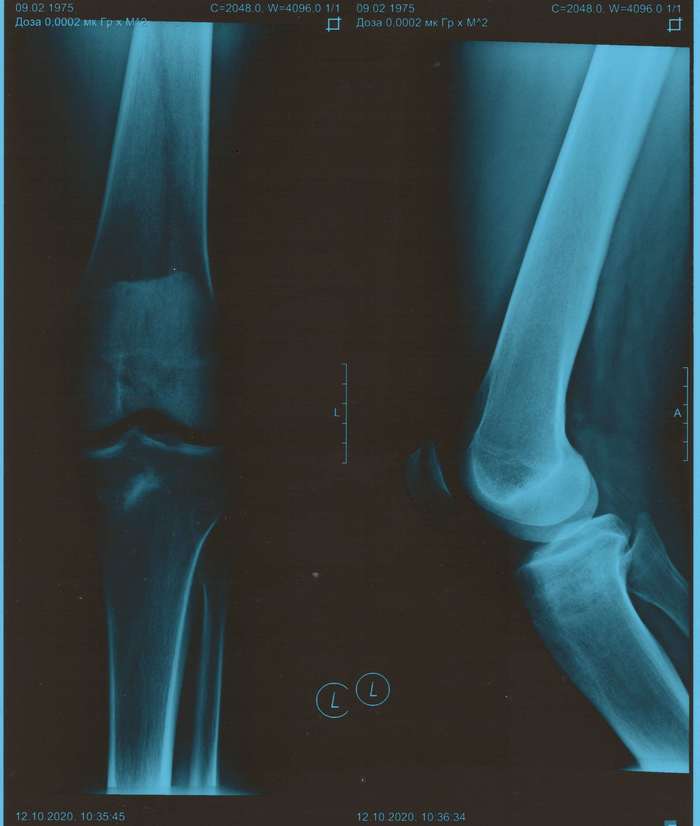

Начальная стадия патологии не всегда заметна визуально, но рентген показывает углы отклонения от биомеханической оси. Чем больше угол – тем больше степень патологии, тем сложнее ее лечить. Последствия варуса и вальгуса плачевны: артроз, остеохондроз, сколиоз, неправильная походка, плоскостопие. В самых тяжелых ситуациях человеку грозит инвалидность.

- рентген кс 1 - картина артроза 1 ст

- рентген кс 2 - картина гонартроза 0-1 ст